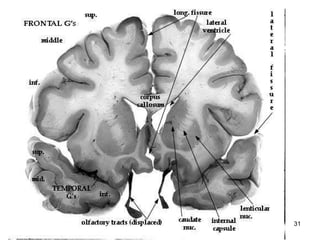

Interior of the cerebrum  Cerebral cortex is composed of  nerve   cell   bodies  on the surface –  grey   matter Inside the cerebrum are the  nerve   fibres  (tracts) which connect the various lobes –  white   matter   The afferent and efferent fibres linking the different parts of the brain and spinal cord are:- Arcuate fibres  –  interconnecting   fibres  between the different lobes of the  same   hemispheres Commisural   fibres  – connecting  one   hemisphere   to   the   other  e.g.  corpus   callosum Projection   fibres  – which  connect  the cerebral  cortex   to  grey matter of  lower   parts  of the brain and the spinal cord e.g. the  internal   capsule

A section of the cerebrum showing some connecting nerve fibres

Basal Ganglia This area of grey matter lies deep within the cerebral hemispheres Consist of  the  caudate nucleus ,  putamen  and  globus pallidus .  They are functionally important for  controlling voluntary movements and establishing postures .  It influences skeletal muscle tone When they are altered - say in disorders like Huntington disease or Wilson disease - the person has unwanted movements, such as involuntary jerking movements of an arm or leg or spasmodic movement of facial muscles.

The  caudate   nucleus  and  putamen  along with the interposed anterior limb of the internal capsule are collectively known as the  corpus striatum  (i.e. striated body) because of their appearance.  Similarly, the shape of the  putamen  and  globus   pallidus  resembles a lens, and they are collectively called the  lenticular nucleus .

Internal Capsule Consists of  projection   fibres  – fibres connecting the cerebral cortex with the lower parts of the brain and the spinal cord Lies deep within the brain Between   the basal ganglia and the thalamus All the  impulses  passing  to and from the cerebral   cortex  are carried by the fibres in the internal capsule The motor fibres within the internal capsule form the  pyramidal   tracts  (otherwise called the corticospinal tracts) The pyramidal fibres cross to the other side at the level of the medulla oblongata (called  decussation )

Interior of thecerebrum Cerebral cortex is composed of nerve cell bodies on the surface – grey matter Inside the cerebrum are the nerve fibres (tracts) which connect the various lobes – white matter The afferent and efferent fibres linking the different parts of the brain and spinal cord are:- Arcuate fibres – interconnecting fibres between the different lobes of the same hemispheres Commisural fibres – connecting one hemisphere to the other e.g. corpus callosum Projection fibres – which connect the cerebral cortex to grey matter of lower parts of the brain and the spinal cord e.g. the internal capsule

A section ofthe cerebrum showing some connecting nerve fibres

Basal Ganglia Thisarea of grey matter lies deep within the cerebral hemispheres Consist of the caudate nucleus , putamen and globus pallidus . They are functionally important for controlling voluntary movements and establishing postures . It influences skeletal muscle tone When they are altered - say in disorders like Huntington disease or Wilson disease - the person has unwanted movements, such as involuntary jerking movements of an arm or leg or spasmodic movement of facial muscles.

Internal Capsule Consistsof projection fibres – fibres connecting the cerebral cortex with the lower parts of the brain and the spinal cord Lies deep within the brain Between the basal ganglia and the thalamus All the impulses passing to and from the cerebral cortex are carried by the fibres in the internal capsule The motor fibres within the internal capsule form the pyramidal tracts (otherwise called the corticospinal tracts) The pyramidal fibres cross to the other side at the level of the medulla oblongata (called decussation )